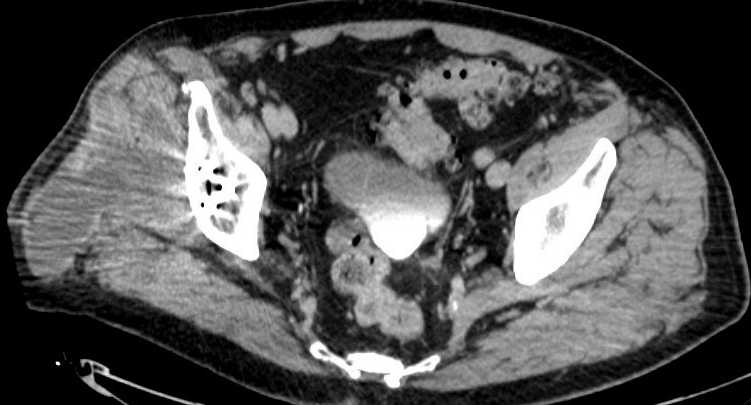

MRI / CT

CT demonstrating large fluid collection around THA